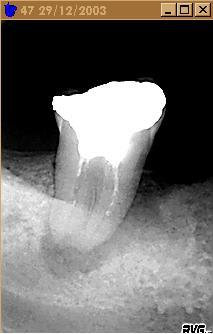

24/02/2005 à 20h03

non, je peux la garder, pourquoi pas, mais certainement pas en pilier de bridge.

alhoun

24/02/2005 à 20h28

la preuve.

Monsieur sal1oq - Eugenol